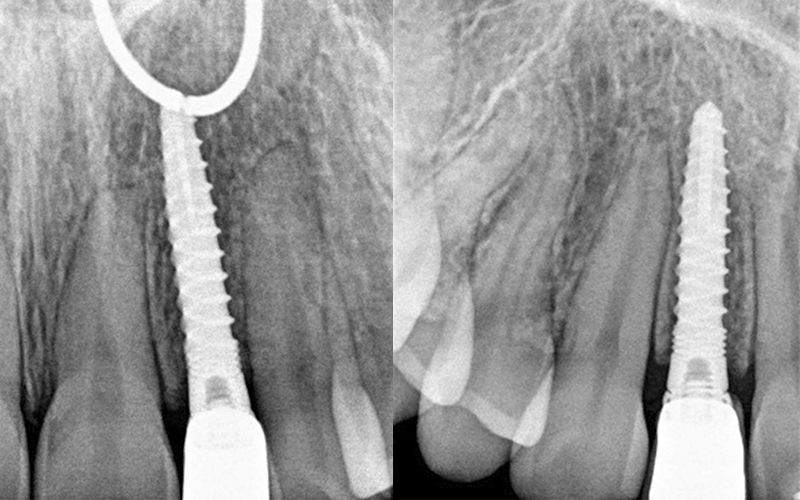

Al cabo de todo este tiempo se realizó un CBCT maxilar para iniciar la planificación de la cirugía de colocación de dos implantes en posición de 12 y 22. Durante el análisis de las imágenes radiográficas, tal y como indican las mediciones que se realizaron, se observó una limitación de espacio en sentido mesio-distal entre 11 – 13 y 21 – 23, que iba a impedir la colocación de dos implantes estándar de 3.3 mm de diámetro.

Dadas las circunstancias y para buscar una resolución óptima del caso, se decidió utilizar implantes Biomimetic Pearl de diámetro reducido de 2.8 mm de Avinent Implant System. Estos mini-implantes disponen de una línea protésica para rehabilitaciones unitarias y, dentro de su amplia gama, encontramos el que se ajustaba mejor a las exigencias del caso, permitiendo mantener perfectamente la distribución de espacio para poder respetar la biología de la rehabilitación.

Se llevó a cabo la cirugía de colocación simultanea de los implantes Pearl de 2.8 x 13 mm en posición de 12 y 22 siguiendo el protocolo indicado por la casa comercial. Estos fueron colocados con éxito a pesar de que las condiciones anatómicas no eran muy ventajosas, consiguiendo 30 Ncm de torque en ambos.